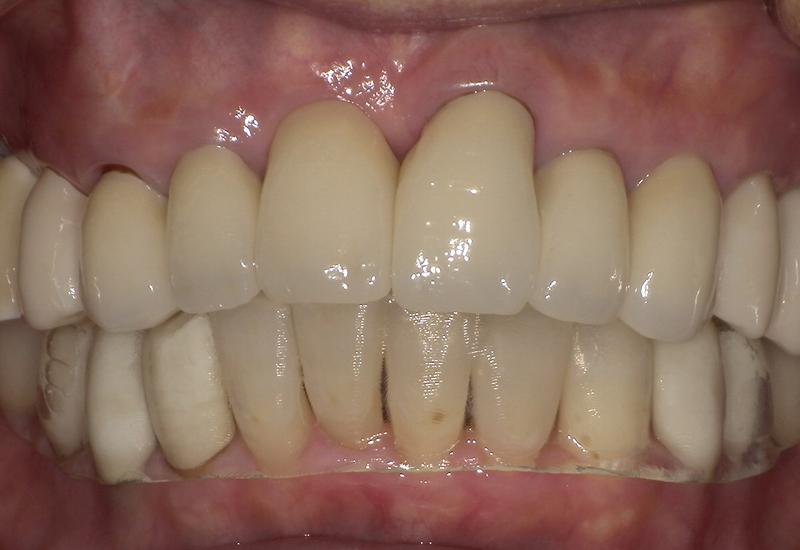

症例① シェイプメモリーアライナーによる下顎の前歯の矯正

治療期間 7ヶ月

治療時の年齢/性別 68歳 / 女性

かかった治療費 440,000円

治療方法 シェイプメモリーアライナー

注意点・詳細

• 根管治療をしてある歯はなるべく動かさない

• 下の前歯の歯の形を少しだけ小さく整えた